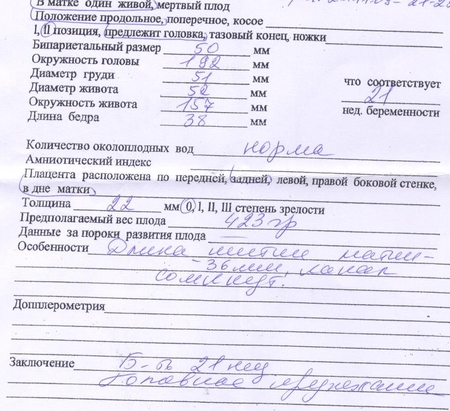

жду мальчика, 23 неделя

а по поводу толщины плаценты ничего не сказали? а то у меня 23 было в 16 недель. Гиня не нашла у себя таблицы, но вроде говорит толстовато

сказали всё в норме...0 степень зрелости обведена,значит хорошо=)

http://bono-esse.ru/blizzard/Aku/UZI/dsb7.html вот нашла такую табличку...может и толстовата,но там норма в 16 нед-18,55 ( 13,8—24,3)..посмотрите с врачом как в след узи будет

Помню какое это счастье читать такие листочки.Здоровья вам!!!